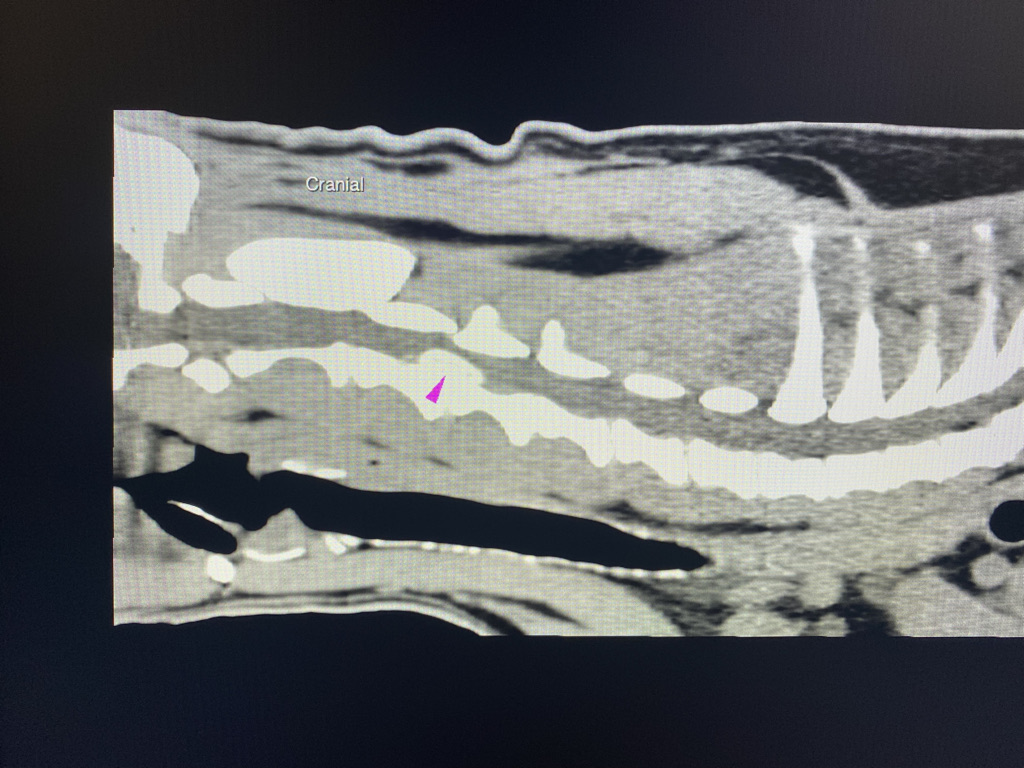

Advanced imaging with computer tomography (CT) or Magnetic Resonance Imaging (MRI) as well as hospital facilities would be required for these cases

Advanced imaging with computer tomography (CT) or Magnetic Resonance Imaging (MRI) as well as hospital facilities would be required for these cases